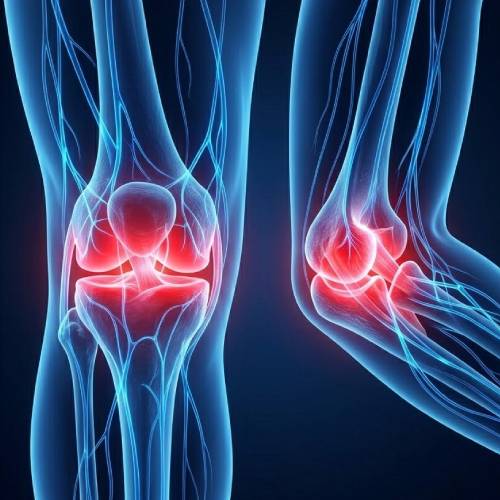

Reduces Discomfort

Helps significantly improve physical comfort and structural body balance.